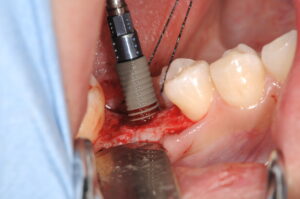

右下に埋入しているところです。親水性の表面を持っているために、血液が上がってきます。